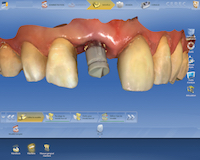

Pour la planification prothétique, le logiciel de CFAO nous permet de modéliser la forme de la future restauration à partir d’une empreinte optique de la situation initiale.

La position des implants est enregistrée à l’aide de transferts numériques et la restauration peut être réalisée soit au laboratoire de prothèse, soit au cabinet dentaire si celui-ci est équipé d’un système de CFAO directe et si la restauration est unitaire.